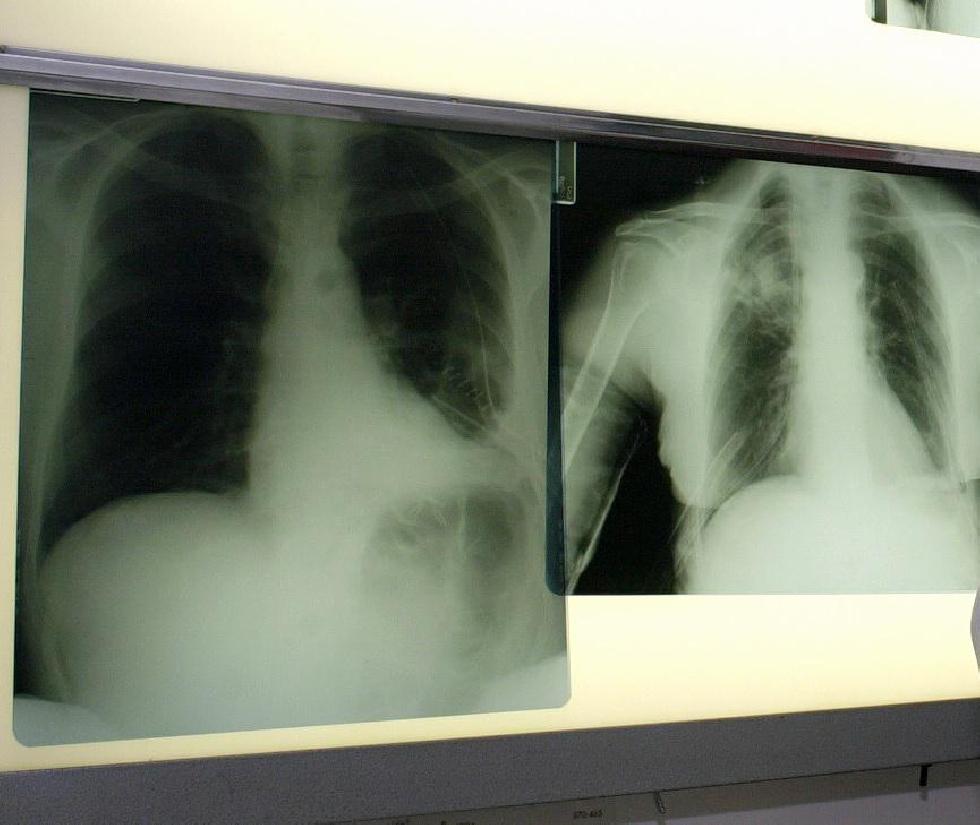

Il tumore al polmone è una delle neoplasie più diffuse, in Italia è la terza più frequente negli uomini e la seconda nelle donne, e causa un numero di decessi superiore a quello di qualunque altra forma di cancro. Grazie alla ricerca scientifica, negli ultimi anni è stato però possibile individuare numerose alterazioni molecolari che sono alla base del suo sviluppo e che possono rappresentare dei target terapeutici. Fra queste l’alterazione a carico del gene Alk (Anaplastic Lymphoma Kinase) – un riarrangiamento dovuto alla fusione di due frammenti di geni – presente nel 5-7% dei pazienti con tumore del polmone non a piccole cellule (Nsclc), con una maggiore incidenza in quelli più giovani (sotto i 50 anni) preferenzialmente – ma non esclusivamente – non fumatori. In presenza dell’alterazione viene prodotta una proteina mutata che promuove la crescita tumorale e la metastatizzazione delle cellule neoplastiche.

La capacità di raggiungere l’encefalo consente a lorlatinib di agire sulle metastasi cerebrali facendole regredire. “Purtroppo circa la metà dei pazienti Alk-positivi sviluppano metastasi cerebrali nel corso della loro malattia – sottolinea Federico Cappuzzo, direttore Uoc Oncologia medica 2 Istituto nazionale tumori ‘Regina Elena’ di Roma – Avere a disposizione un farmaco che ha un’azione sull’encefalo addirittura superiore a quella esercitata in altri organi è un elemento di grandissima rilevanza perché molto spesso le metastasi encefaliche si associano a sintomi e disabilità che inducono a un peggioramento importante della qualità di vita. Il farmaco, inoltre, è ben tollerato, con eventi avversi generalmente ben gestibili”.